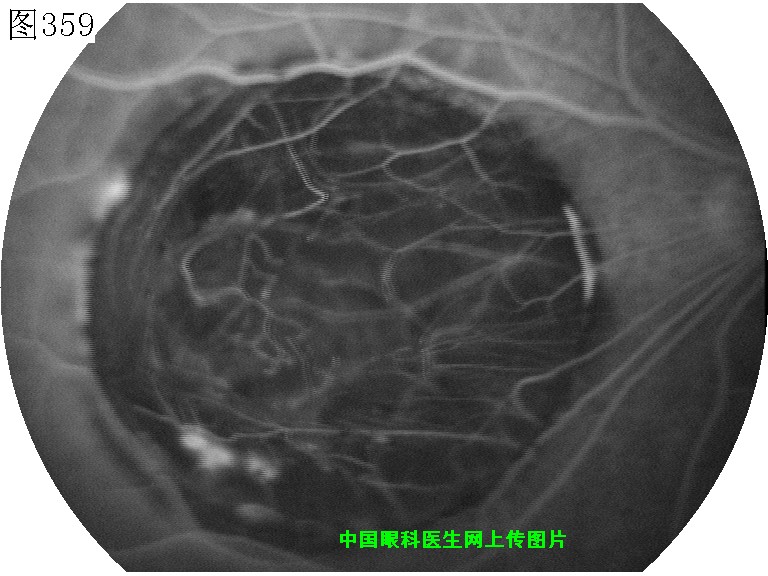

357 358 359 360